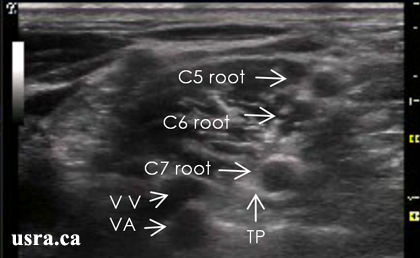

肌间沟入路